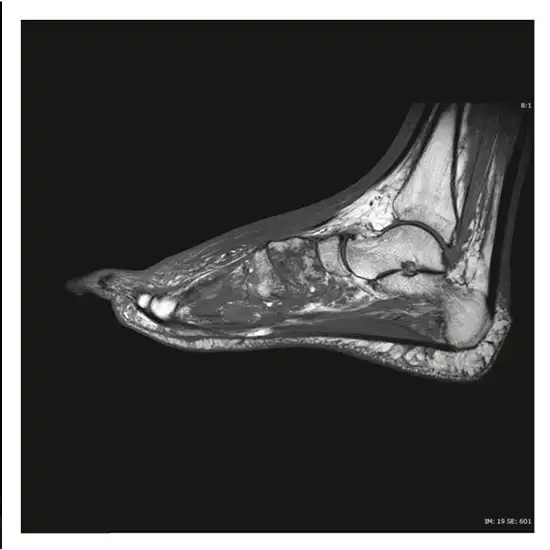

An MRI of the left foot with contrast shows the bones and surrounding soft tissues such as tendons, ligaments, muscles, and blood arteries. The contrast improves the MRI's sensitivity and diagnostic accuracy by making inside organs more visible.

This test diagnoses broken or fractured foot bones, osteoporosis, deformities, unusual bone growth, and arthritis (inflammation of the joints).